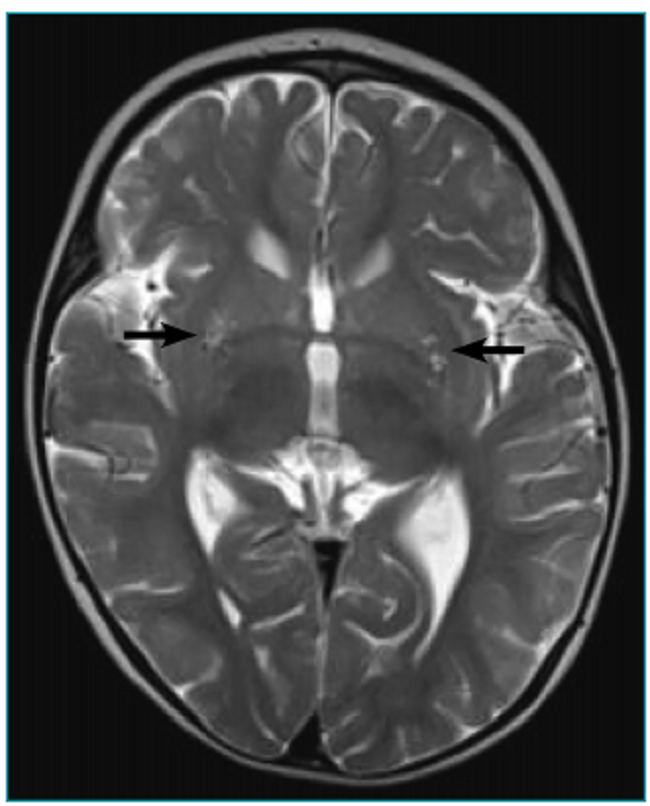

Perante a suspeita clínica e laboratorial de SL, deve ser realizada a ressonância magnética cranioencefálica (RM-CE). Os achados mais comuns, na imagem em T2, são as hiperintensidades focais, bilaterais e simétricas localizadas tipicamente nos gânglios da base (especialmente no putâmen) e/ou no tronco cerebral. Outras áreas frequentemente envolvidas são tálamo, substância nigra, núcleo rubro, tronco cerebral, cerebelo, substância branca cerebral ou medula espinhal.2,6,7,13 Essas lesões, evidentes tanto na imagem cerebral como nos estudos anatomopatológicos, são atribuídas à depleção de ATP, com consequente lactoacidose, congestão vascular, hipóxia e, finalmente, necrose. O envolvimento preferencial das regiões subcorticais é atribuído à maior vulnerabilidade à lactoacidose, que parece ser secundária ao seu suporte vascular, as arteríolas penetrantes.2,4,14

Nas imagens da RM-CE em T2, observava-se hipersinal lenticular, bilateral, expressando-se no putâmen e havendo dúvida em relação ao globo pálido esquerdo, o que sugeriu o diagnóstico de doença metabólica, principalmente na ausência de intercorrências durante a gestação e periparto (Figuras 1 e 2). Do estudo metabólico realizado, destacavam-se hipocitrulinemia de 5 µmol/L (normal 15 a 30 µmol/L) e hiperlactacidemia de 3,0 mmol/L (normal 0,5 a 2,2 mmol/L). A paciente apresentava piruvato sérico, amônia e cromatografia dos ácidos orgânicos normais. Executaram-se também potenciais auditivos evocados do tronco cerebral, eletrocardiograma e ecocardiograma, que não revelaram alterações. Foi avaliada por oftalmologista, revelando exame normal.